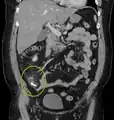

| A fecalith marked by the arrow which has resulted in acute appendicitis. | |

A fecalith is a stone made of feces. It is a hardening of feces into lumps of varying size and may occur anywhere in the intestinal tract but is typically found in the colon. It is also called appendicolith when it occurs in the appendix and is sometimes concomitant with appendicitis.[1] They can also obstruct diverticula. It can possibly form secondary to fecal impaction. A fecaloma is a more severe form of fecal impaction, and a hardened fecaloma may be considered to be a giant fecalith. The term is from Greek líthos=stone.[2]

A small fecalith is one cause of both appendicitis and acute diverticulitis.